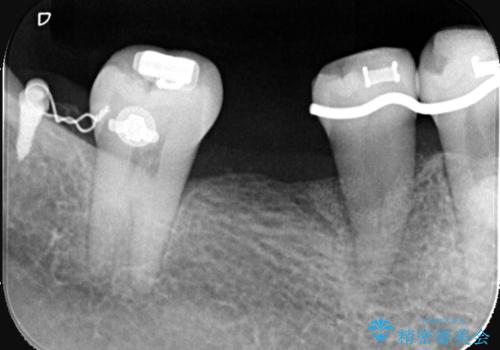

【1Dayインプラント治療! 低侵襲で短期間での治療】 咬むと歯が痛い! 歯根破折